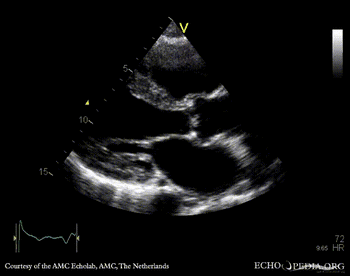

A4CH: enlarged atria and ventricles A3CH: severe aortic and mitral regurgitation